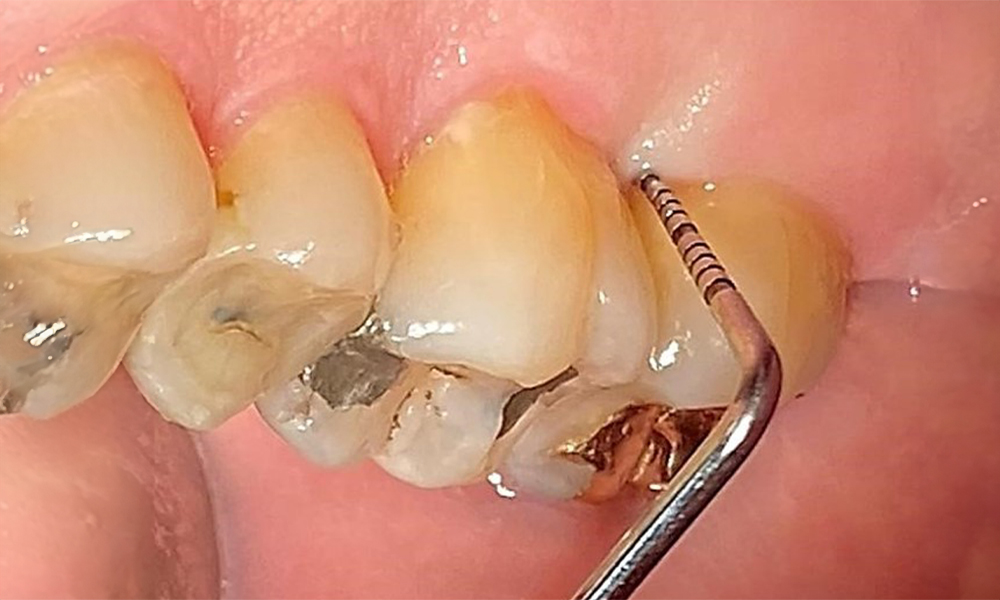

The documentation of periodontal findings, including pocket depth probing and bleeding status, is mandatory during each dental appointment due to the presence of periodontitis (Fig. 8). This will record the individual therapeutic needs and facilitate a rapid response to any progression of the pre-existing periodontitis.

Probing to document the findings in tooth 27 mesiopalatal. © Dr R. Krapf

Fig. 8: Probing to document the findings in tooth 27 mesiopalatal. © Dr R. Krapf

Detailed periodontal findings, including the documentation of pocket depths, bleeding on probing, recessions, furcation involvement and degree of loosening, must be examined annually.